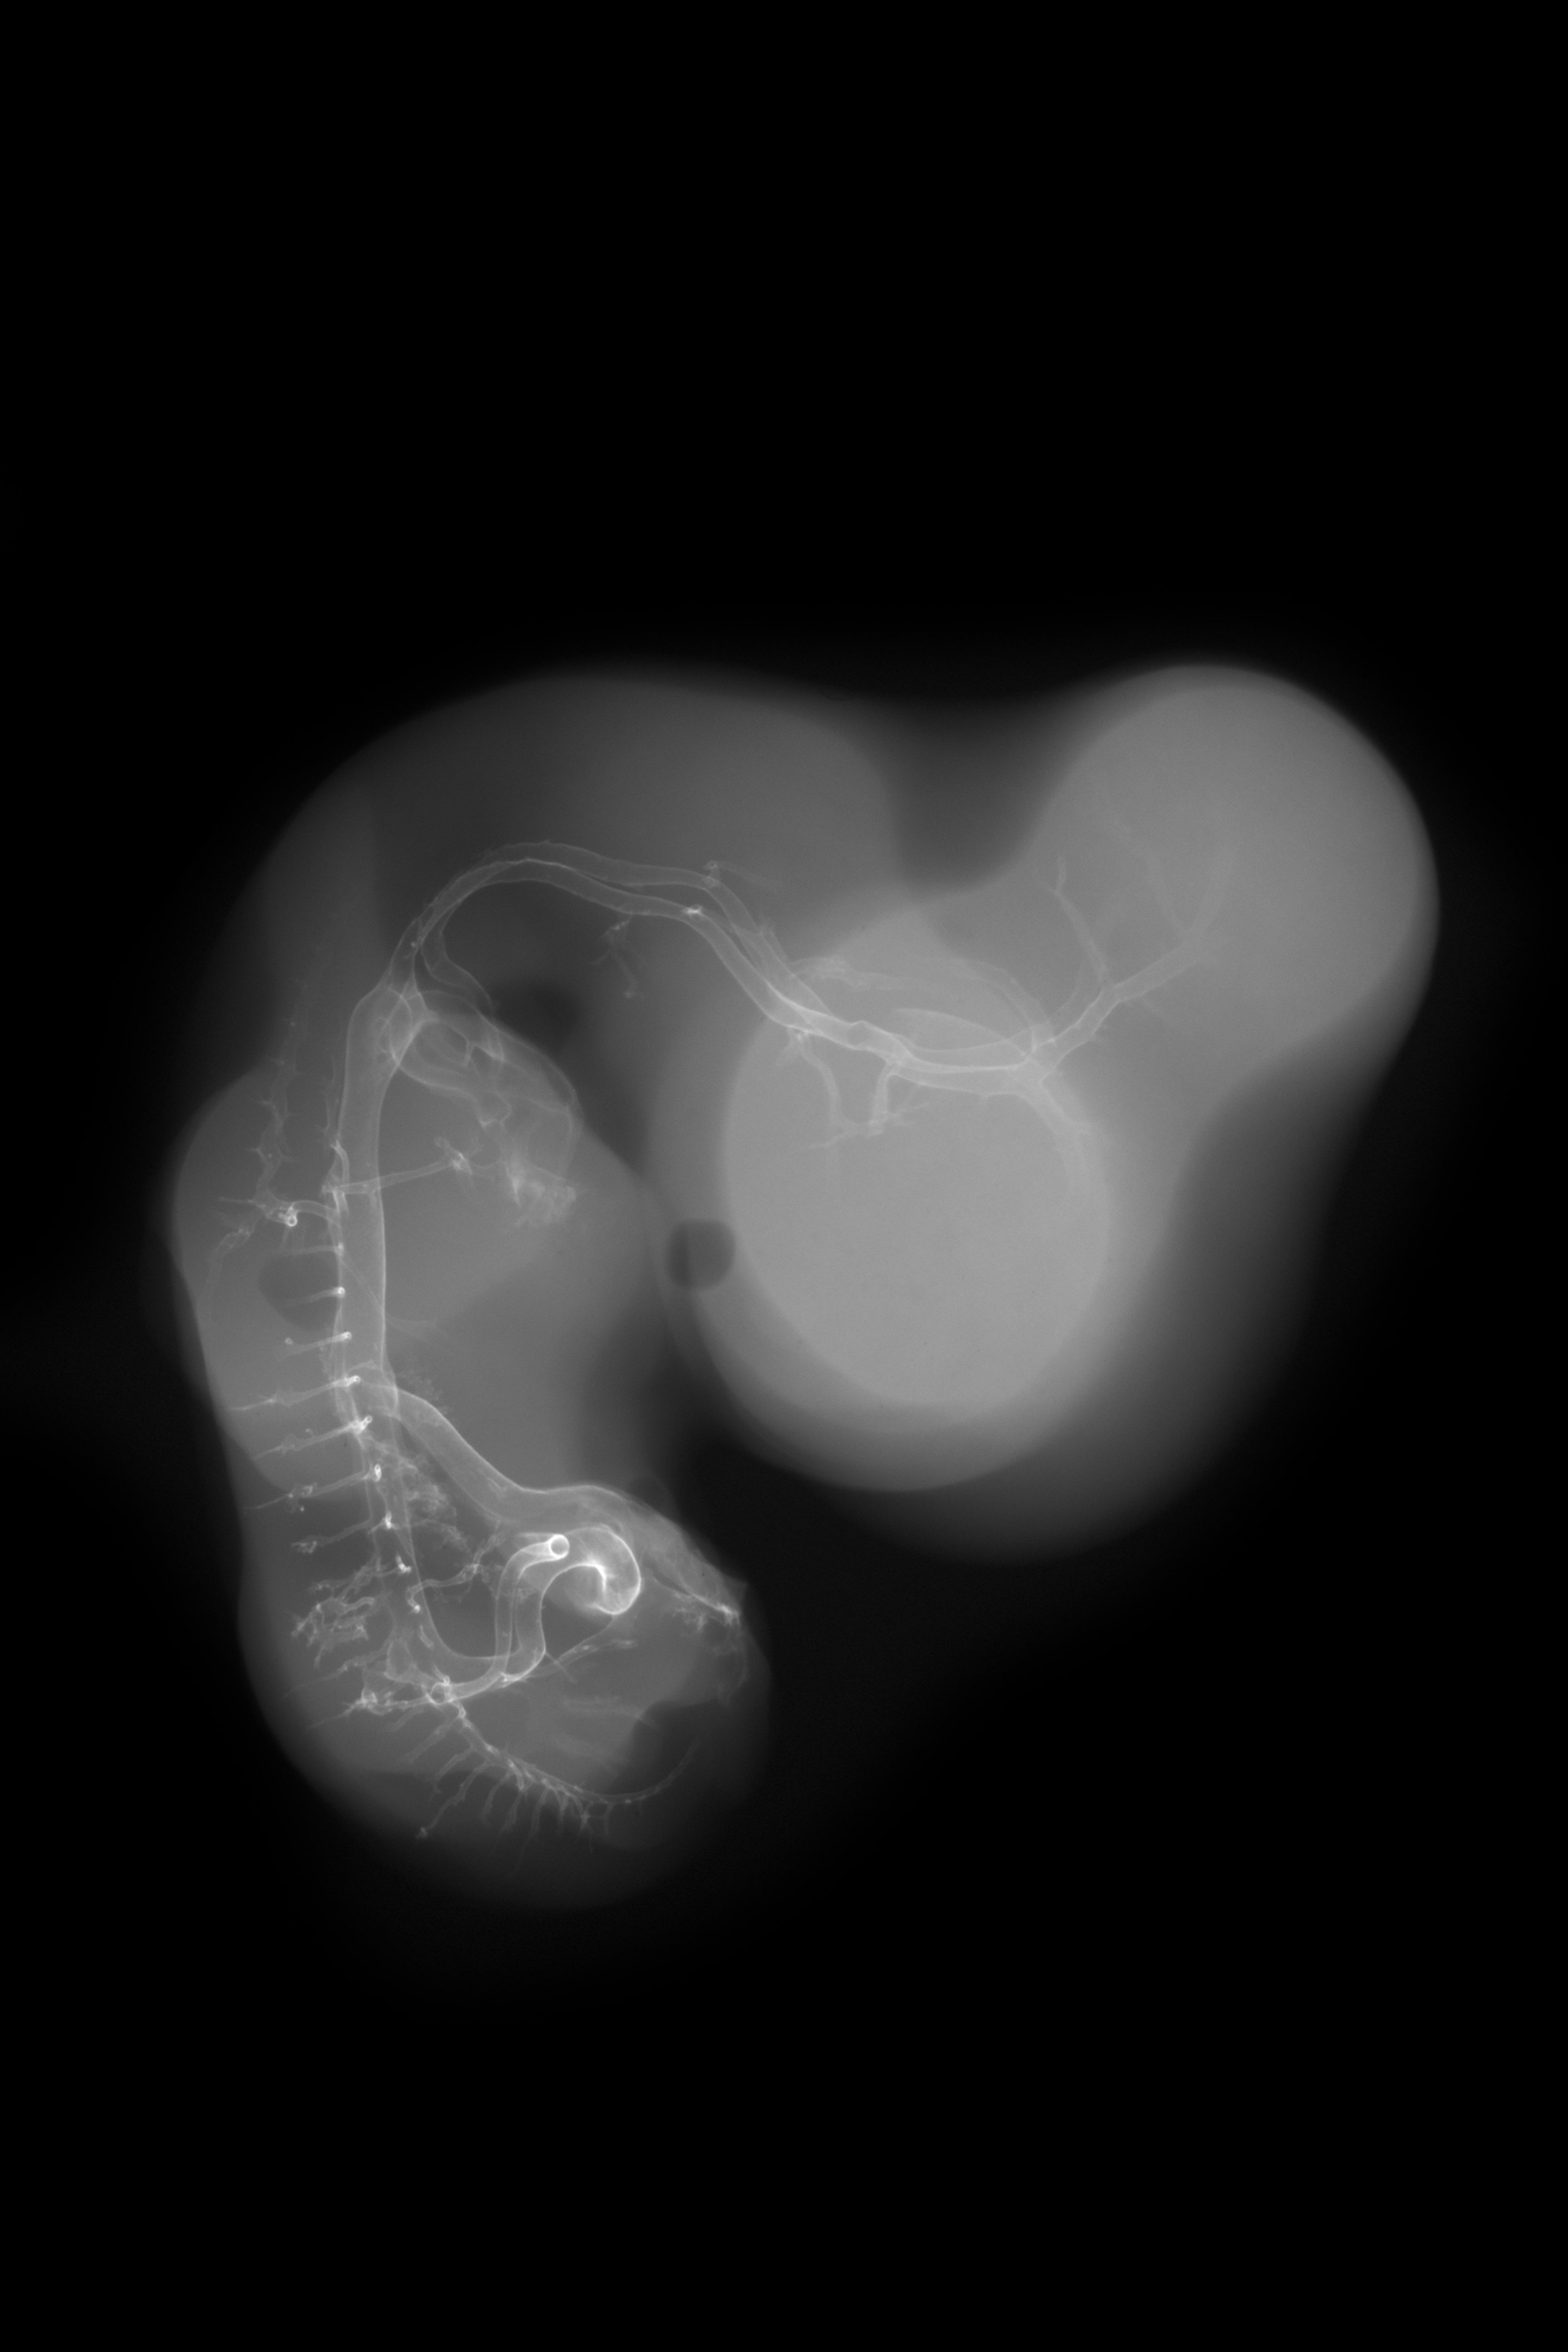

X-Ray Micrographs